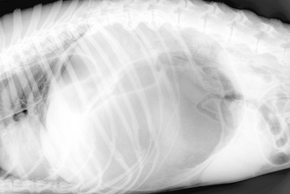

Les calculs urinaires chez le chien

Loin d’être une fatalité, les calculs urinaires chez le chien restent handicapants pour votre poilu. En effet, négligés, ces cailloux présents dans le système urinaire causent de lourdes complications et des douleurs pour votre chien. Mais alors, comment les traiter ? Quelles en sont les causes ? Et comment reconnaître leur présence ? Les réponses dans cet article !